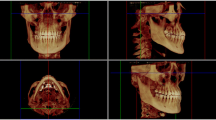

With the help of individual CT- or CBCT-based DICOM data, both the spatial configuration and the thickness of the remaining bone were analyzed and transferred into the simulation software to perform the preoperative “virtual osteotomy.”

Three-dimensional finite element analysis (FEA) was used to examine deformation and stress-strain response of the anatomical model of the skull under the applied osteotomies and the distractor load before the surgery. The skull was segmented with MIS software (Mimics Innovation suite V20.0, Materialise NV, Leuven, Belgium) which allows analysis of individual differences of bone thickness (Fig. 1).

For finite element analysis, ANSYS Mechanical APDL 19.2 (ANSYS, Inc., Canonsburg, PA, USA) was used. The STL model of the individual skull with a specific osteotomy configuration was imported into ICEM CFD (ANSYS, Inc., Canonsburg, PA, USA) for meshing. Tetrahedral unstructured grids were generated in ANSYS ICEM CFD 19.2 based on the STL geometry of the skull.

A partially or complete opening of the lateral sinus wall and disconnection of the midpalatal suture, as advised by Lines, could be performed individually in the software environment (Fig. 2). Mesh refinement and mesh smoothing were generated to ensure a high finite element quality. An input file with the FE mesh was exported for the solver. The tetrahedral mesh file was imported into the ANSYS Mechanical APDL software application. With the programming language APDL (ANSYS Parametric Design Language), the definition of material properties and boundary conditions was performed. For the bone material, Poison’s ratio of 0.3 and a modulus of elasticity of 15000MPa are defined. The transversal distraction of both palatal halves was simulated by applying a force of 150N at the endpoints of the distractor which were individually adjusted.

The whole workflow with the meshing of bone geometry, the finite element model generation, and the simulation was performed automatically (Fig. 3).